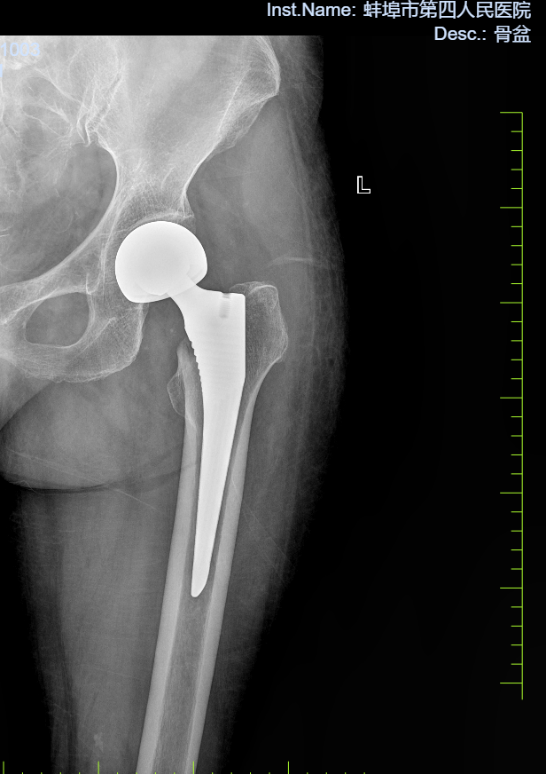

病例二:患者,女,84岁,因“摔伤致左髋部疼痛伴活动受限3天”入院。诊断:左侧股骨颈骨折;行左侧人工股骨头置换术,手术顺利,术后恢复良好,顺利出院。

左侧股骨颈骨折 术前X线片 左侧股骨颈骨折 术后X线片